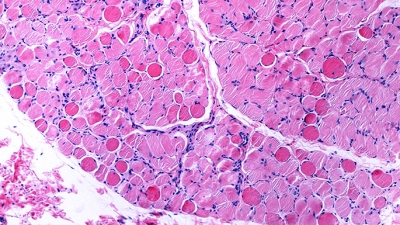

Muscular dystrophies are genetic disorders characterized by muscle regenerative deficits, extensive muscle loss and fibrosis. One such disease, Duchenne muscular dystrophy (DMD), is a severe and relentlessly progressive myopathy that results from mutations in the X-linked DMD gene that disrupt the mRNA reading frame and prevent translation of the muscle structural protein, dystrophin. In DMD, the lack of dystrophin leads to chronic muscle degeneration, inflammation and fibrosis, resulting in a loss of muscle structural integrity and myofiber death. A promising genetic therapeutic strategy for DMD and other neuromuscular diseases is 'exon skipping' through the use of antisense oligonucleotides (AOs). This class of drug allows for ‘exon skipping’ of the mutated exons in the patient’s dystrophin gene to restore a functional, truncated dystrophin protein, and is currently the only approved genetic therapy for the treatment of DMD. A major focus of our research investigates how the complex pathological processes in DMD and muscular dystrophies modulate the delivery and therapeutic efficacy of antisense chemistries and gene therapies to develop novel delivery strategies to improve the pharmacokinetics and efficacy of these therapeutic agents for muscle diseases.

Skeletal and cardiac muscle disease pathogenesis Therapeutic targets for muscular dystrophies